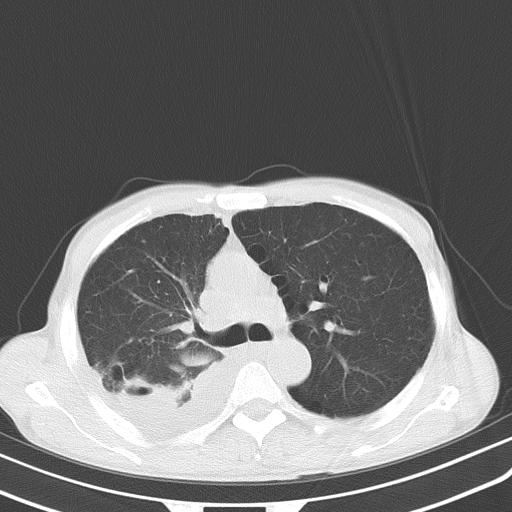

右肺继发型tb并右侧tb性胸腔炎,右侧胸腔大量积液并右下肺膨胀不全,慢支肺气肿、多发肺大泡。建议抽胸水实验室检查并复查排除恶性在占位。

右上肺继发型肺结核,右胸腔中等量积液。

左上肺大泡。

结核的基础上有纵隔淋巴结肿大,右侧有胸水,但右侧纵隔反而窄,说明有肺有不张。

再就是右下肺有块影,和不张混合,还是不能除外肺癌。

1)右肺继发型肺结核。2)左肺胸膜下多发性肺大泡。3)右侧胸腔积液。